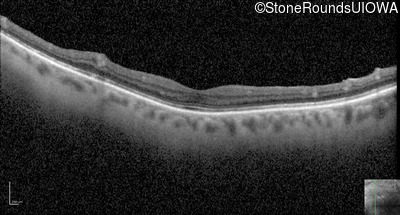

Optical Coherence Tomography - Left - 20/50 +3

Exemplar / OCT Stack

OCT Stack